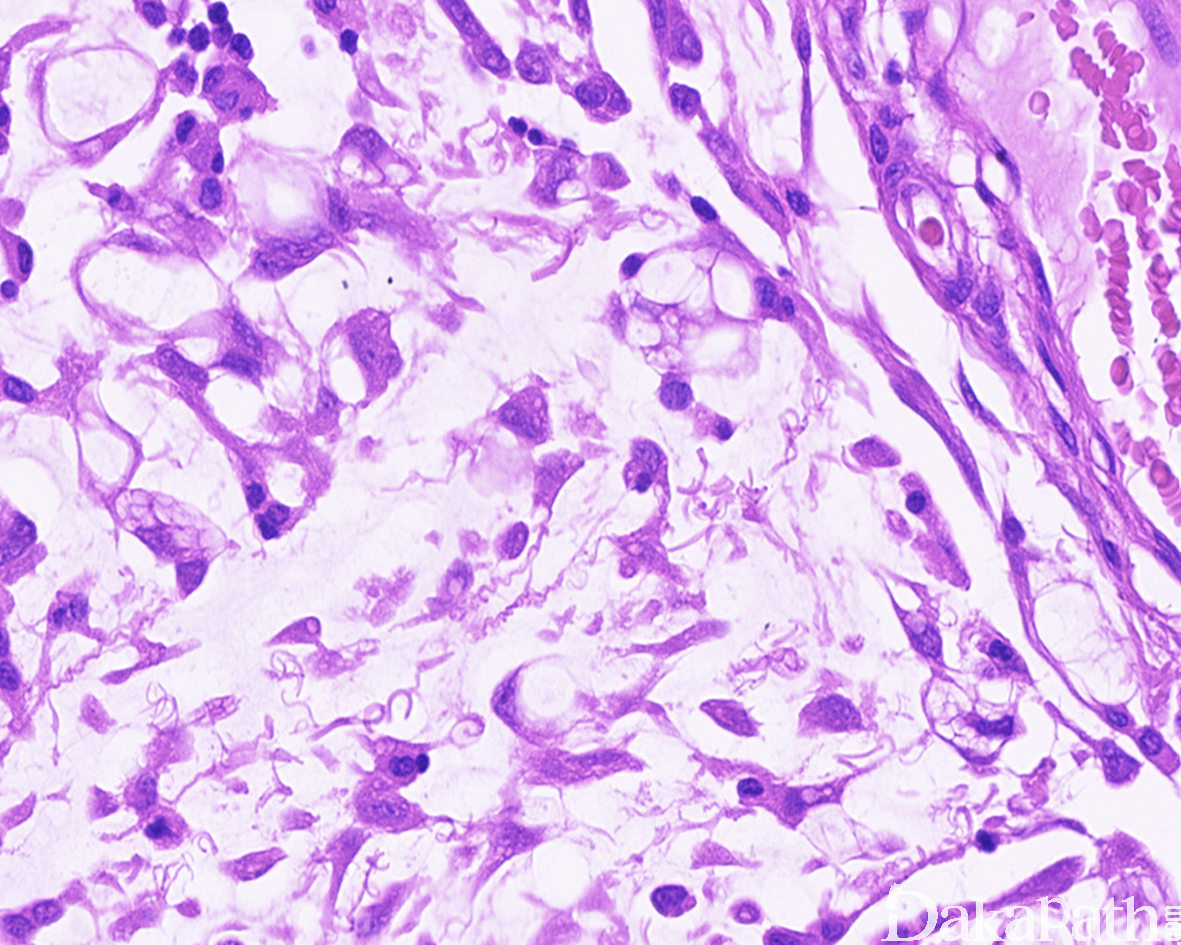

- 高度恶性黏液纤维肉瘤:

- 肿瘤大部分区域由排列致密的梭形细胞和多形性细胞组成,核分裂像易见,并可见病理性核分裂像,形态上类似经典的纤维肉瘤或恶性纤维组织细胞瘤,但在局部区域,仍可见到低度恶性的黏液纤维肉瘤成分,两者之间可见移行;

- 偶可见上皮样肿瘤细胞,呈圆形或多边形,胞质嗜伊红色,核呈圆形,染色质呈空泡状,可见明显的核仁,与经典的黏液纤维肉瘤相似;

- 上皮样的瘤细胞也可显示明显的多形性,并可见病理性核分裂像;

- 也可见到胞质内含有黏液的假脂肪母细胞。